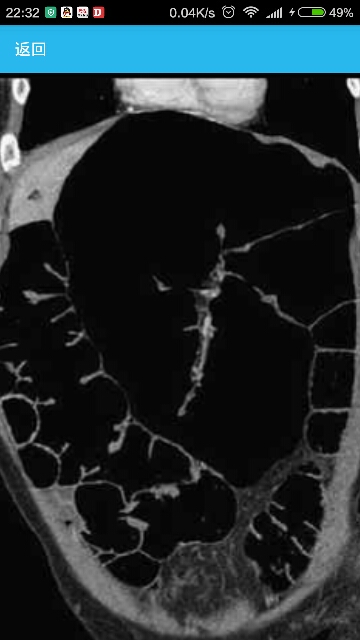

辅助检查CT肠管造影检查显示,患者结肠脾曲扩张严重,未见梗阻性肿物和肠扭转(见图1和图2)。高分辨率肛门直肠球囊扩张测压检查显示,患者肛门括约肌压力较高,存在肛门直肠抑制性反射,当外部牵拉力达到564g时仍不能将直肠内球囊拉出(正常值<200g)。